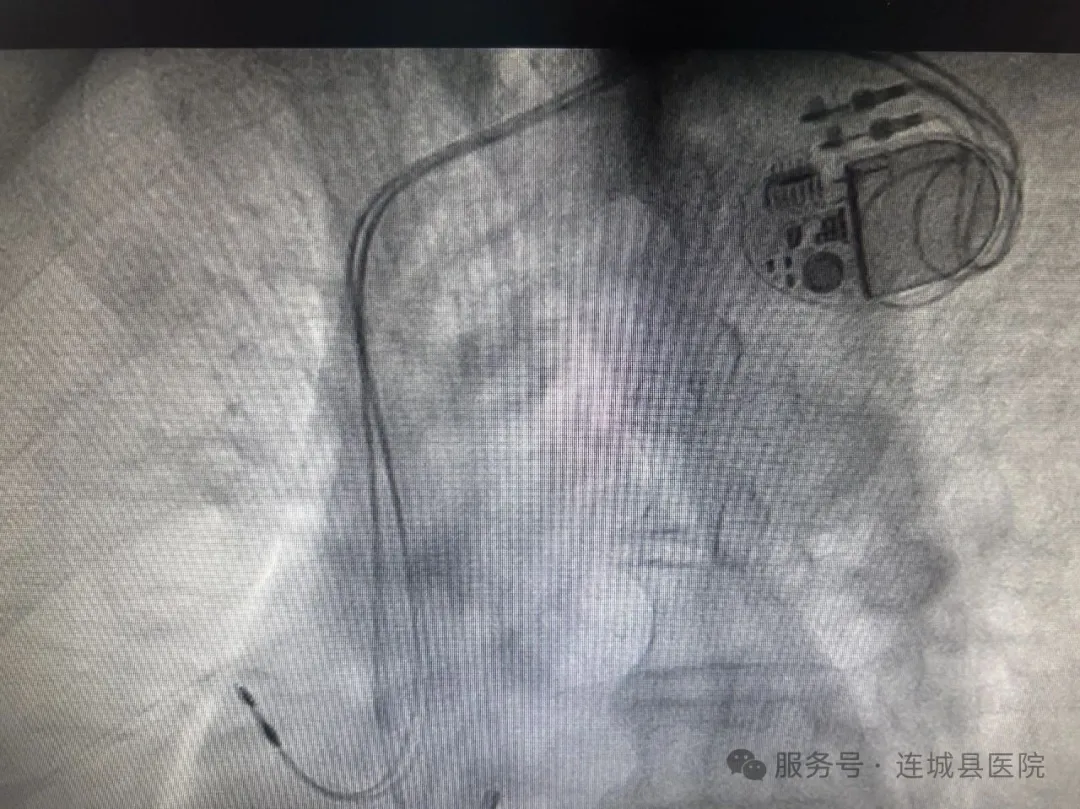

双腔起搏器筑起“心”长城

5月13日晨,心内科手术团队在余福玲副主任医师的指导下,将一枚硬币大小的双腔起搏器植入患者锁骨下区。术中测试显示,起搏阈值、阻抗、感知灵敏度等核心指标均表现优异。随着心脏节律的恢复正常,连城县总医院首例永久起搏器植入术圆满成功,填补了县域内该技术领域的空白。